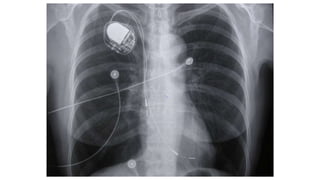

A 61-year-old man presented with worsening right thoracic pain and dyspnea three days after being discharged from cardiology following pacemaker implantation for sick sinus syndrome. A 60-year-old woman with an implanted pacemaker presented with dizziness and fainting. A 77-year-old woman who had a pacemaker implanted for symptomatic sinus bradycardia presented one week later with continuous chest pain. An elderly patient presented 6 months after pacemaker implantation with a recurrence of exertional shortness of breath.